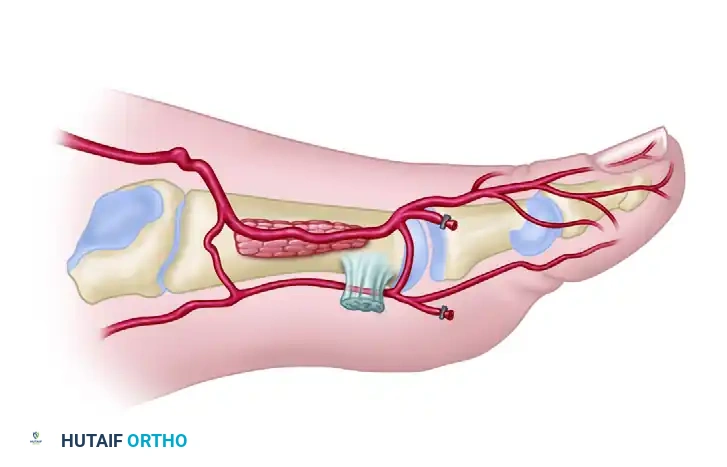

6. Distal Dissection and Flap Mobilization

- Continue dissecting distally, maintaining the plane superficial to the paratenon over the EDL tendons.

- Identify the extensor hallucis brevis (EHB) tendon, which crosses obliquely over the DPA.

- Surgical Option: The EHB tendon can be transected and carried with the flap. However, leaving the EHB muscle belly on the foot can provide valuable vascularized coverage over the underlying bone and tendons, improving the donor site bed.

- As dissection proceeds distally into the first web space, keep the FDMA superficial to the plane of dissection, ensuring it remains attached to the skin paddle.

- Ligate and divide the distal arterial branches to the toes at the distal margin of the flap.